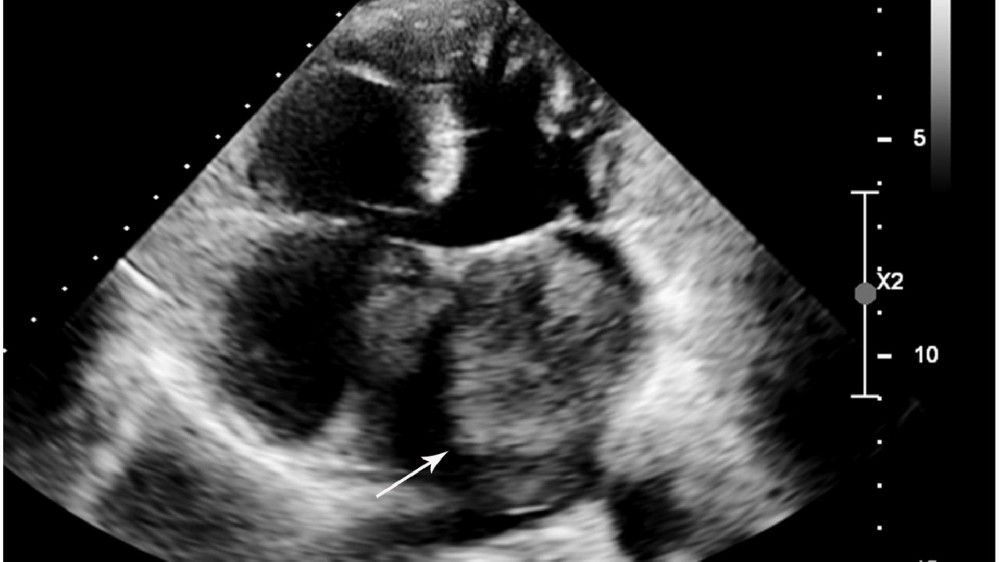

心臟癌(心臟肉瘤)的分期和存活率

瞭解不同階段有助於釐清預後、決定治療方法,以及管理診斷出患有下列疾病的病患的期望值 心臟癌(心臟肉瘤).準確的分期有賴於影像研究、病理評估和臨床參數,以協助醫療團隊發展個人化治療,確保最佳效果。